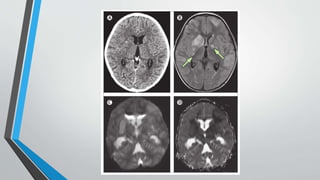

IMAGEN

• Convencionalmente no utiles para diagnostico en etiologias virales y

bacterianas.

• TUBERCULOSIS:

• TAC se puede observar exudados hiperdensos basales, engrosamiento de meninges.

• Hasta en 30% de pacientes puede ser NORMAL.

• RNM superior aTAC.

• Pueden detectarse zonas de infarto tempranos.

• Con Gadolinio pueden demostrarse tuberculomas presentes en hasta 75% de

pacientes.

• Las anomalias mas comunes por este metodo son: engrosamiento de las meninges e

hidrocefalea.

IMAGEN • Convencionalmente noutiles para diagnostico en etiologias virales y bacterianas. • TUBERCULOSIS: • TAC se puede observar exudados hiperdensos basales, engrosamiento de meninges. • Hasta en 30% de pacientes puede ser NORMAL. • RNM superior aTAC. • Pueden detectarse zonas de infarto tempranos. • Con Gadolinio pueden demostrarse tuberculomas presentes en hasta 75% de pacientes. • Las anomalias mas comunes por este metodo son: engrosamiento de las meninges e hidrocefalea.